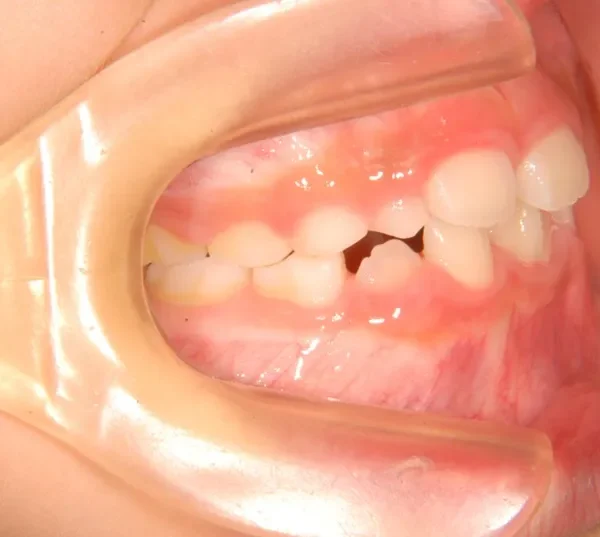

初診時年齢 小学校2年生 (男性) 主訴 癒合歯・永久歯が生えるスペースがない

診断名 叢生 装置名

状態 永久歯が生える隙間がない(叢生)

ガタガタ・でこぼこに生えている(叢生)

上下の歯並びが狭く、永久歯の生える隙間がありません。

右下に癒合歯があり 上下の歯並びのアーチが悪くなっています。